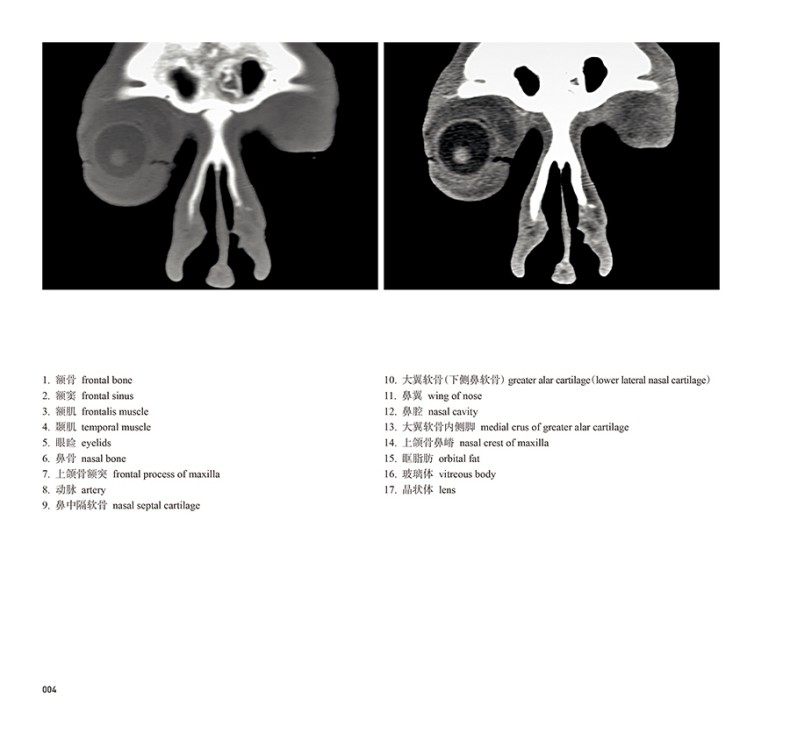

本书从数据集每隔1.2mm选取一幅图像,截取眼、耳、鼻及毗邻颅底的局部区域图像,共112幅图像。同时配以相应部位的CT图像对照。本书特色是断层解剖图利用数字图像处理技术优势,放大并清晰展示眼、耳、鼻及毗邻颅底断面的局部区域结构,组织色泽真实,甚至能够清晰显示肌肉纹理、筋膜纹路等细节结构,图像质量高于美国《人体断层解剖学彩色图谱》(引进版)类似图谱图像质量。对眼科、耳鼻咽喉科医生理解相关解剖结构有较大帮助。